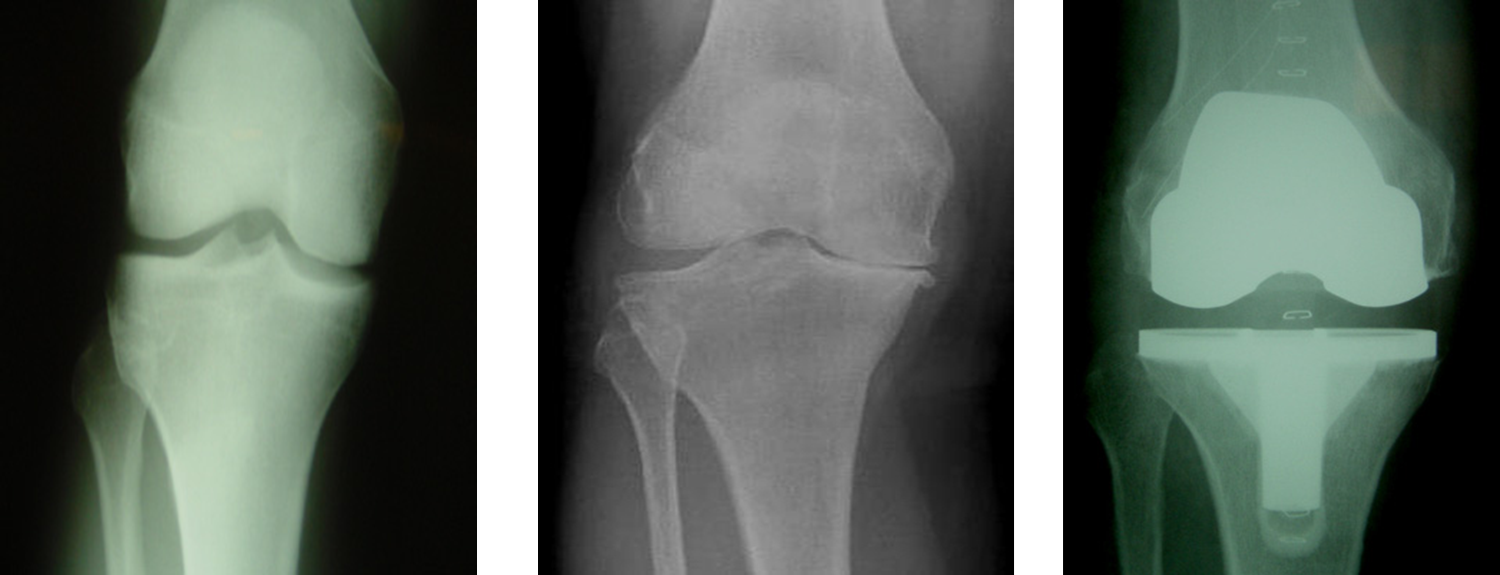

Osteoarthritis

(Degenerative Joint Disease)

Generalized disorder pathologically characterized by loss of joint cartilage and reactive new bone formation.

Cause: traumatic, stress to joints

Complications: joint pain, stiffness, trouble using joints for walking, grasping, etc

Radiographic Appearance: irregular narrowing of joint spaces and development of small bony spurs (osteophytes)

•Knee – articular ends become increasingly dense and joint narrowing is asymmetric

•Fingers – affect distal joints, marginal spurs produce well defined bony protuberances (can palpate and see knobby appearance)

•Hip – asymmetric narrowing of joint space (superiorly and laterally)

Technical: Advance Stage – Subtractive disease

•May require slight decrease

Prognosis: Some patients are unaffected by osteoarthritis while others can be severely disabled.

•Joint replacement surgery for some results in the best long-term outcome.